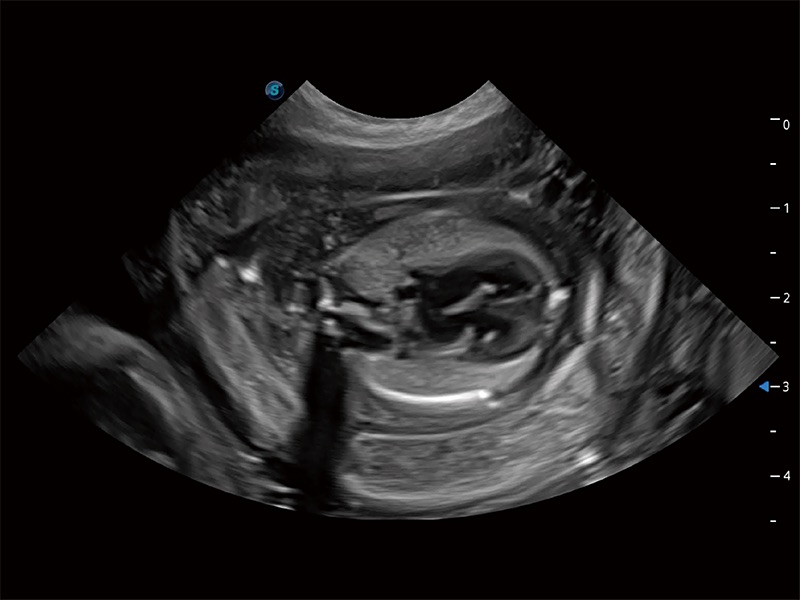

动物是人类最亲密的朋友和最值得信赖的伙伴。美狮贵宾会官网也一直致力于探索动物专用的超声影像解决方案。全新推出的ProPet系列,是美狮贵宾会官网在动物超声影像智能化、专业化、精准化的一次跨越式革新。动物不能用言语来表述自己的不适,通过超声影像,ProPet系列搭建了动物医生与不同物种沟通的“桥梁”,为动物医生注入了“治愈之力”。 ProPet 80 是美狮贵宾会官网匠心打造的一款高端动物专用彩超,采用性能卓越的全新硬件架构,极大提升超声系统的运行效率和数据处理能力,帮助动物医生从容应对日益增多的挑战性病例和日益多样化的临床需求。

高性能和先进的临床应用工具可以为动物医生提供临床信心。ProPet 80 搭载了先进的腹部和浅表应用工具,帮助医生在日常临床实践中发挥前所未有的作用。